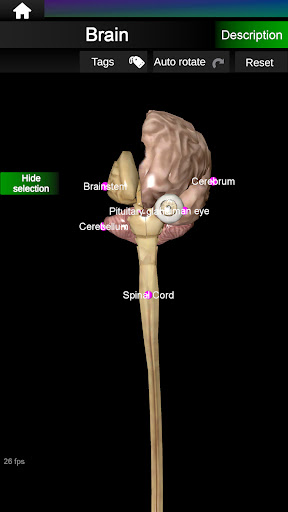

* Мозок, який включає головний мозок, мозочок і стовбур мозку.